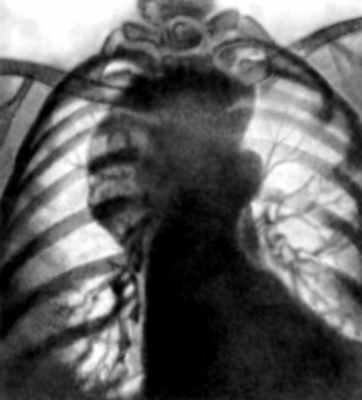

Больной Л., 39 лет, поступил в клинику института 20/III 1953 г. с жалобами на периодические тупые боли в левой надсосковой области и одышку при ходьбе. Эти симптомы у больного появились несколько лет назад и мало беспокоили его. С диагнозом «опухоль средостения» больной был направлен к нам в институт.

Общее состояние хорошее. Температура нормальная. Со стороны внутренних органов каких-либо отклонений от нормы не отмечается. Кровь и моча без существенных изменений. При рентгенологическом исследовании слева в ретростернальном пространстве переднего средостения, непосредственно за грудиной (на уровне первого-третьего межреберья) опеределяется овальной формы однородное, интенсивное затемнение размером около 5X8 см. Контуры его четкие, на большем протяжении правильно выпуклые, в нижнем отделе слегка бугристые. В боковой проекции, а лучше — в правой косой по всему контуру затемнения выявляется очень интенсивная линейная тень обызвествления, и все образование напоминает куриное яйцо в скорлупе.

На рентгенокимограммах видны зубцы сосудистого типа с амплитудой в 2 мм, местами резко деформированные. В остальном — рентгенологическая картина нормальной грудной клетки.

Данные клиники и характерная рентгенологическая картина, особенно наличие обызвествления капсулы, дали нам основание диагностировать дермоидную кисту. Оперативное вмешательство (удаление кисты, Е. С. Лушников) подтвердило наш диагноз. Удаленная киста имела бугристую поверхность. Капсула ее была почти сплошь обызвествлена. Содержимое кисты — кашицеобразная кофейного цвета масса с большим количеством холестерина и неизмененных эритроцитов.

В данном случае имелись характерные рентгенологические признаки дермоидной кисты и среди них наиболее важным был признак обызвествления капсулы.

В диагностике большое значение имеет рентгенологическое исследование (при расположении Д. в средостении наиболее полную информацию дает пневмомедиастинография в сочетании с томографией, Д. брюшной полости выявляют с помощью пневморетроперитонеума и пневмоперитонеума). Рентгенологическим признаком Д., локализующегося в области черепа, являются углубления и дефекты с гладкими четкими контурами в костях черепа, обусловленные давлением Д. на кость. Д. пресакрального пространства может вызвать краевой дефект передней стенки крестца и отклонение копчика кзади. Д. средостения (рис. 2) обычно представляется в виде однородной овоидной тени в верхнем или среднем его отделе; латеральные его контуры, выступающие в легочное поле, обычно гладкие или слегка волнистые; медиальные сливаются с тенью средостения или (при больших Д.) выступают слева от него; нередко отмечается обызвествление стенки Д., в его полости могут выявляться различные костные включения. В отличие от целомических и паразитарных кист конфигурация Д. не меняется при дыхании и натуживании. Отсутствует активная пульсация его стенки. Д. брюшной полости имеет вид объемного образования, специфические рентгенологические признаки отсутствуют. Для диагностики применяют также эхотомографию (см. Ультразвуковая диагностика); эффективным методом является компьютерная Томография.

Рентгенограмма грудной клетки больной с дермоидом средостения: правая косая проекция, стрелкой указан смещенный дермоидом к позвоночнику контрастированный пищевод">

Рис. 2б). Рентгенограмма грудной клетки больной с дермоидом средостения: правая косая проекция, стрелкой указан смещенный дермоидом к позвоночнику контрастированный пищевод.